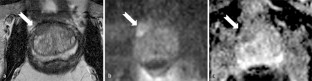

Abb. 1

Abb. 2

Abb. 3